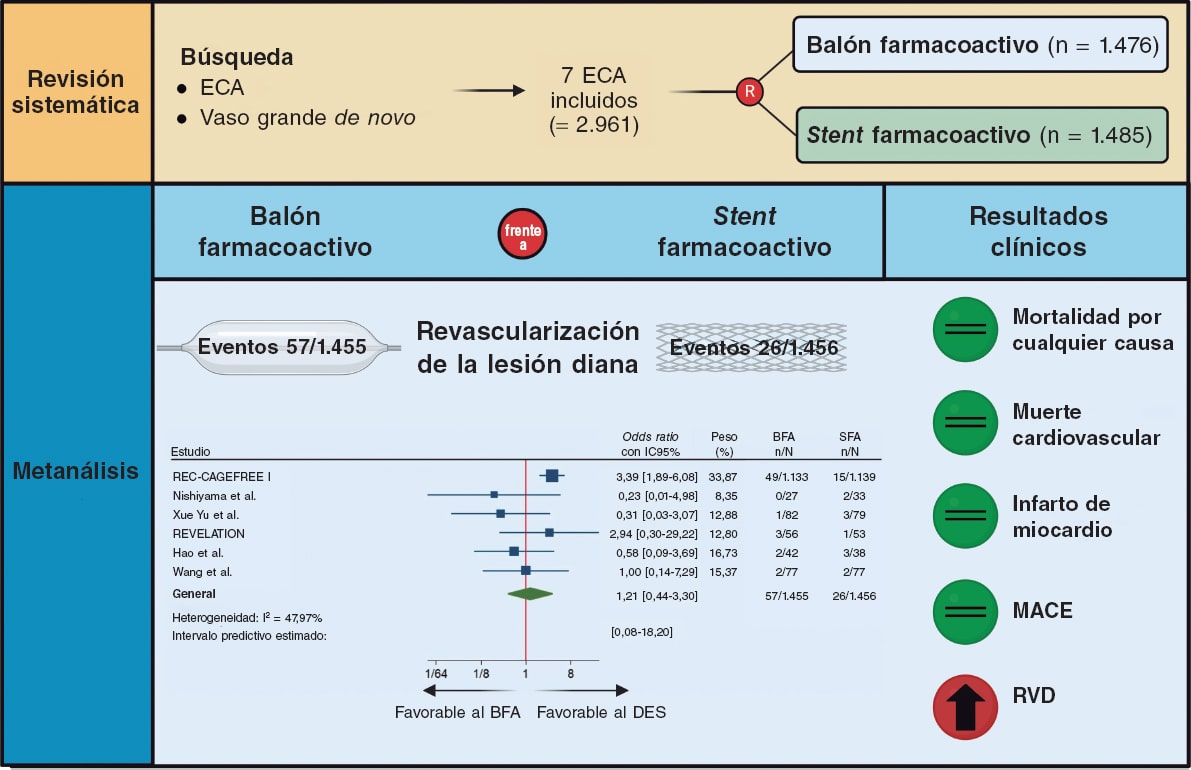

Balones farmacoactivos: a la conquista de la enfermedad coronaria de vaso grande

Artículos originales

Editoriales